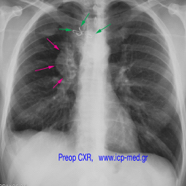

Fourteen yrs before, the patient had elsewhere undergone resection of his 1st right costo-sternal joint by another colleague, who had disarticulated the sterno-clavicular and then sewn it with a steel wire (green arrows in preop images). Histopathology report had failed to identify a chondrosarcoma diagnosis at that old time!

IMAGES 2–6: Preop CXR & CTs,